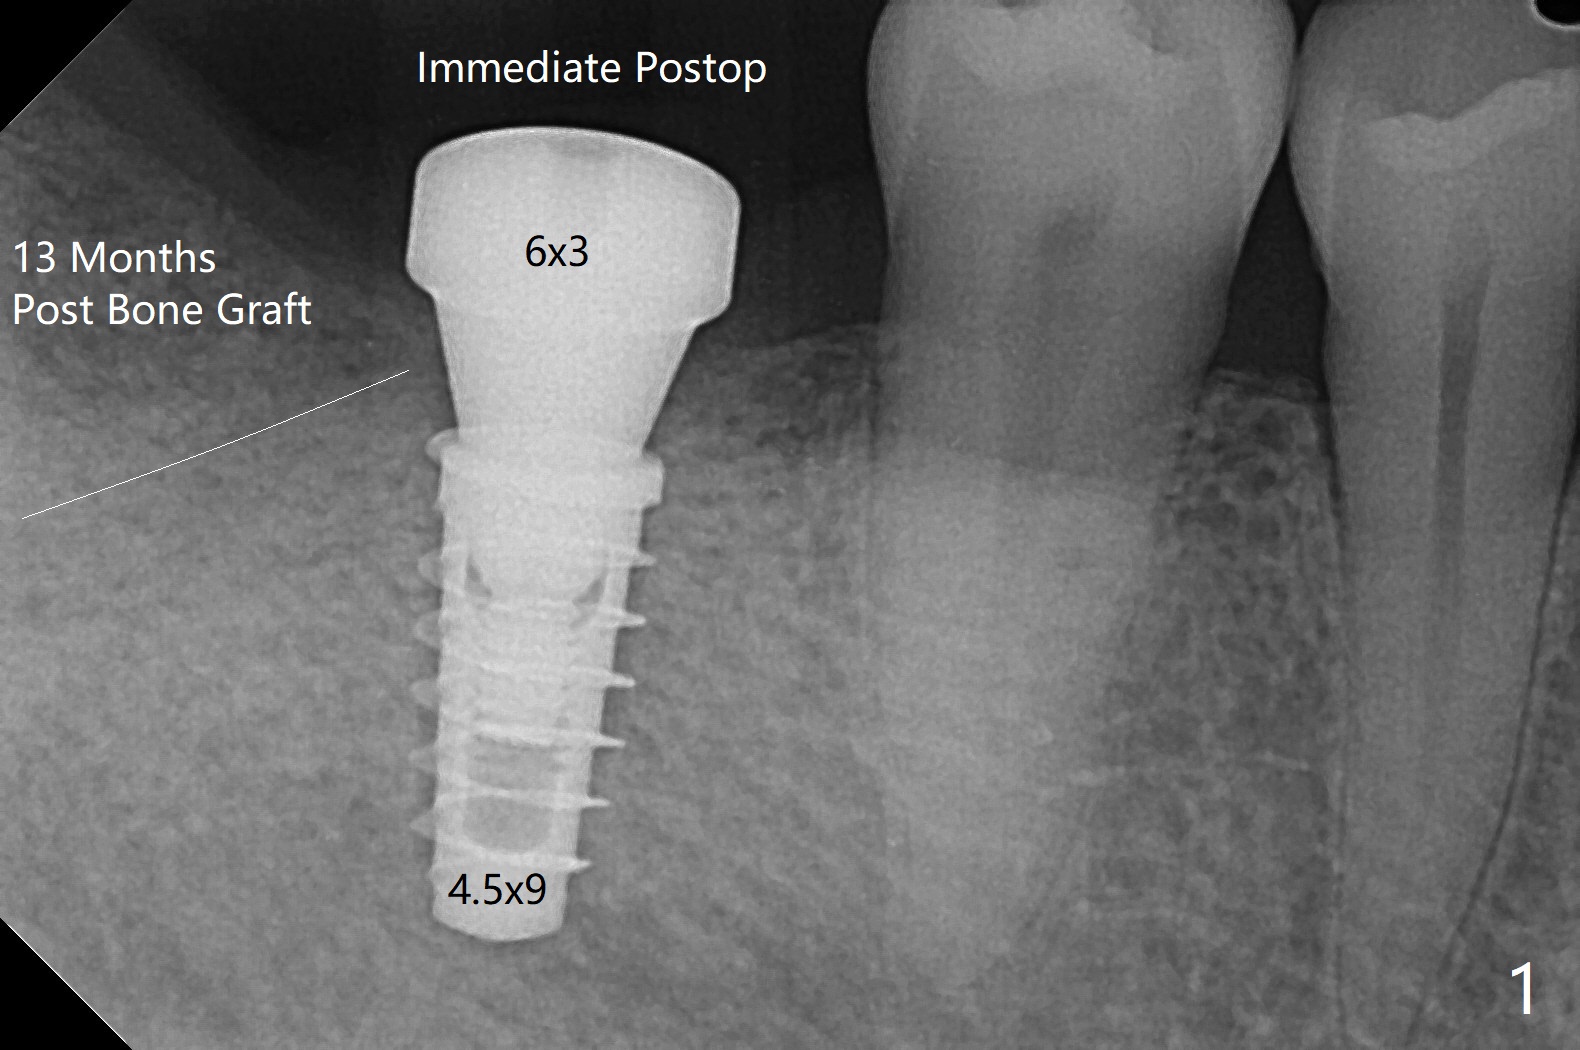

右下7(以前近中倾斜移位)位点保留后13月回来做6导板种植,骨质密度高,钻洞慢,注意灌溉制冷,使用4.5毫米功螺纹钻头后,植入4.5x9毫米植体(图一:牙槽嵴下~1毫米,扭力大约35Ncm)。使用5.5和6.0毫米profile drills后,放置6x3毫米愈合基台,最后植体,基台周围放置自体骨(事先翻瓣)。看样子邻牙植骨(图一:白线)对植牙有帮助。翻瓣缺点是缝合后伤口保护,牙周敷料术后一两天脱落(远中植体最好使用修复基台,不容易脱落),造成病人恐慌,第二次敷料术后第七天脱落,可欣的是伤口术后第八天愈合(图二)。术后四个月更换基台(图三),调整高度后,取模。由于基台边缘龈上,先拧紧(30 Ncm)后粘固,之后不再取出基台。然后对合取模,修改对合牙冠。